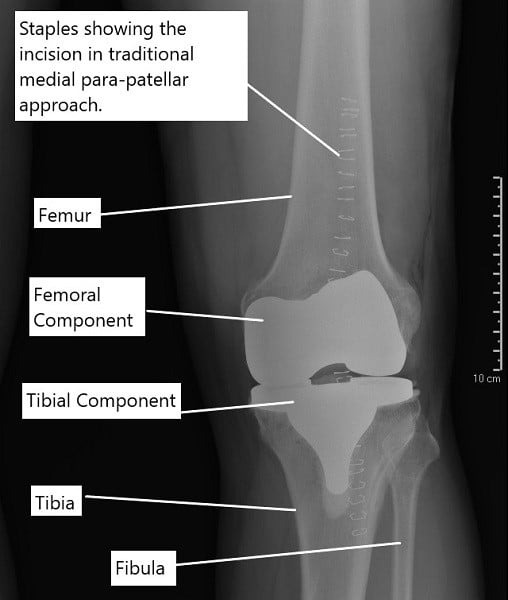

X-ray showing the staples over the incision of a traditional knee replacement done.

Traditional total knee replacement uses a larger incision and allows the surgeon to see the entire joint clearly. The quadriceps tendon is partially opened, and the kneecap is moved aside. The worn bone surfaces are shaped to fit the artificial implants, which are secured with bone cement.

Traditional knee replacement surgery

During a traditional knee replacement surgery, the surgeon gives an incision in front of the knee joint. After dissecting the tissues, the surgeon cuts the quadriceps tendon along the side of the kneecap. A tissue along the side of the patellar tendon (an extension of the quadriceps tendon) is also cut.

The quadriceps tendon attached to the four quadriceps muscles present in front of the thigh. The four quadriceps muscles help in the extension of the leg at the knee joint. The integrity of the muscles, quadriceps tendon, patella, knee joint, and patellar tendon is required for straightening the leg.

The kneecap is then usually everted to get a better exposure of the joint. The surgeon then proceeds to surgically cut the bone ends of the thigh bone and the shin bone. The cuts are made to contour the shape so the prosthetic implants fit over the cut ends.

While the bony preparation of the cut ends is an important aspect of the replacement surgery, the most crucial part in stabilizing the knee joint. Stabilizing the artificial joint requires balancing the forces acting around the knee joint. The diseased knee joint is often deformed (knock knees or bow legs). The deformity is also corrected during the surgery.

After the knee is balanced, metal prosthetic parts are fixed using bone cement on the thigh bone and the shin bone. A high-grade plastic is inserted in between the metal parts to smoothen the motion. The incision is closed in layered and the patient is usually able to walk the evening of the surgery or the next day.